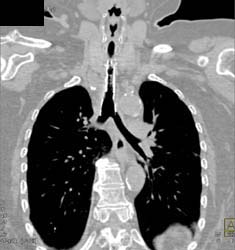

Broken Catheter in Pulmonary Artery